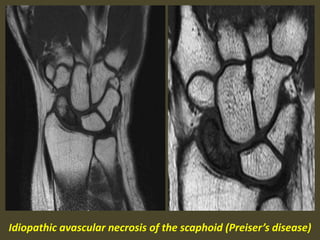

Preiser's disease. Coronal inversion recovery (A) and fast spin echo (B) images:

1. a bone marrow edema pattern in the scaphoid (black arrow) and 2.

avascular necrosis of the proximal pole (white arrow). No fracture is visible.

Idiopathic avascular necrosis of the scaphoid (Preiser’s disease)